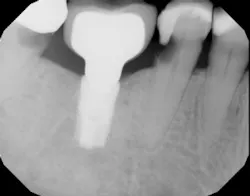

It is imperative for clinicians and teams involved with dental implant care to be aware of implant-induced decay, take necessary radiographs, and perform clinical exams in order to identify open contacts prior to caries development. Once teeth adjacent to implants are afflicted with decay, restoration (figure 2) or even extraction may be warranted (figure 3). To prevent these problems from occurring, individuals who have contributing factors mentioned in this article may benefit from having a screw-retained implant restoration and/or be given an Essix appliance to prevent tooth migration.

Figure 3: This decayed tooth adjacent to an implant requires extraction.